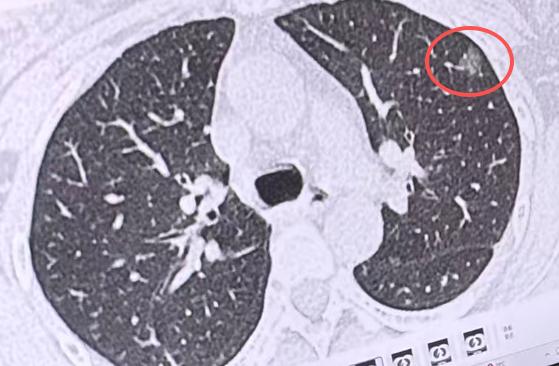

在门诊坐诊这么多年,我最常遇到的情况就是,有人一查出身体里长了结节,立马就慌了神,整个人都没了主心骨,甚至坐立不安。 前阵子,就有一位40出头的中年女士,拿着肺部检查报告来找我,报告上显示,她的肺上长了个结节,不算小,有一公分多。 结合她的检查结果和身体状况,我认真评估后,建议她做切除手术,主要考虑了三个方面: 1、从影像片子上看,这个结节的形态、特征,大概率是肿瘤; 2、这个结节长在肺的外周部位,不像长在肺中央那样难处理,手术切除的时候,对肺部整体的功能影响很小,术后恢复也会比较快; 3、她年纪不算大,身体底子还不错,但这个结节已经长到一公分了,从临床经验来看,后续发生变化的概率不低,早处理更稳妥。 可我刚把手术建议说出口,这位女士瞬间就崩溃了,眼泪一下子就掉了下来,连话都说不连贯。我赶紧停下手里的活儿,慢慢安慰她,让她先别着急、别绝望。 我跟她讲清楚,这个结节即便确实是肿瘤,甚至可以说是肺癌,也属于非常早期的阶段,只要及时做手术切除,治愈率很高,完全能治好。 说真的,能在这个阶段发现问题,其实是不幸中的万幸。要是等到结节变大、发生转移,再去处理,不仅治疗难度增加,患者也要多受很多罪。 我发现,很多患者一听到“手术”两个字,就会焦虑、崩溃,说到底,还是对这种疾病不了解,心里没底,越想越害怕,越怕越慌。 不过也有例外,门诊上经常有患者跟我说:“医生,我之前看过您做的科普视频和文章,对肺结节多少有了解,今天来检查,心里早就有底了,一点都不害怕。” 其实,这就是我一直坚持做医学科普的意义,也是我的初心。 我不想让大家再因为不懂而恐慌,只想通过科普,把正确、科学的肺结节、肺癌相关知识,实实在在地传递给每一个人。 让大家能正确认识这种疾病,知道不同情况该怎么处理,消除那些不必要的焦虑,能坦然面对,用最科学、最稳妥的方式,守护好自己的身体健康。[作揖][玫瑰]